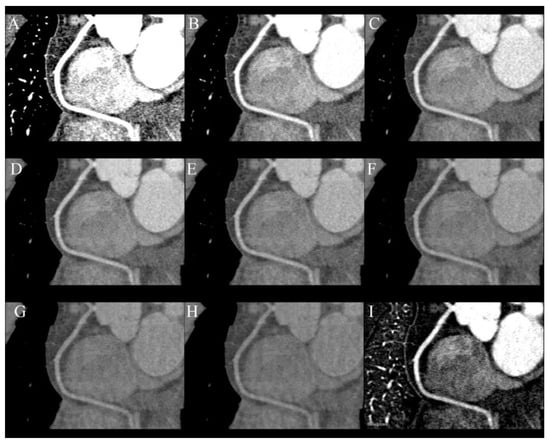

The primary goal of heart CT is the assessment of coronary arteries and improving quality and diagnostic possibilities is the main reason for performing this examination in dual-energy mode (Figure 2A–I). This is possible by reducing the number of blooming artifacts from stents and calcifications. Monoenergetic images, material specific reconstruction and effective Z-number imaging are helpful in reaching that goal [13,34]. The blooming artifacts that originate from stents and calcified plaques are a reason for the overestimation of the degree of stenosis. They can be reduced by VMIs of high energy, e.g., 110 keV, which has been proven to highly reduce artifacts from hyperdense metallic structures, but simultaneously, they are less sensitive to iodine. For that reason, it is essential to assess the lumen of coronary arteries using multiple VMIs. Calcium subtraction is other method of increasing the accuracy of heavily calcified coronary arteries [24,34,35].

Figure 2.

Series of curved MPR of RCA at different energy VMIs: (A)—40 keV, (B)—50 keV, (C)—60 keV, (D)—70 keV, (E)—80 keV, (F)—100 keV, (G)—120 keV, (H)—140 keV. The best contrast to noise ratio is at 60–70 keV images (C,D) Lower energies have higher iodine density but also much higher noise. Higher-energy VMIs (F–H) are less useful due to low contrast density. (I)—curved MPR reconstructed from iodine(water) map can also be used to assess lumen of RCA.